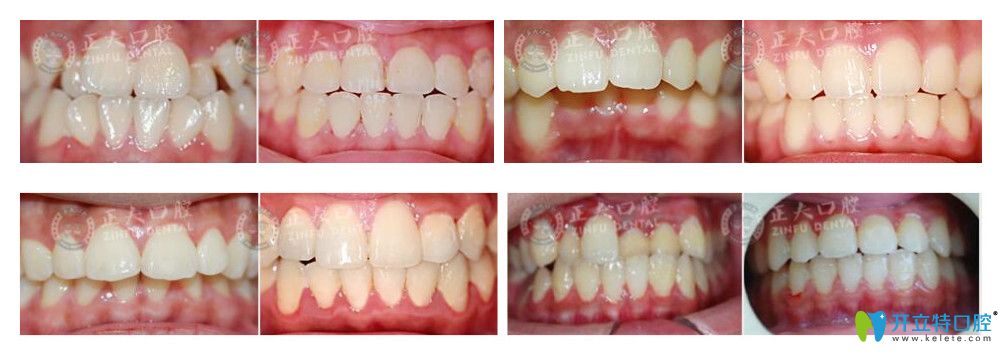

因?yàn)槟壳發(fā)h魔法絲矯正技術(shù)并沒(méi)有普及到所有的口腔,只有很少一部分口腔機(jī)構(gòu)掌握這種先進(jìn)的正畸技術(shù),所以很多人對(duì)該技術(shù)的效果還抱有疑慮,徐國(guó)強(qiáng)院長(zhǎng)曬出了他做過(guò)的一些lh魔法絲矯正案例。

深圳正夫口腔徐國(guó)強(qiáng)lh魔法絲矯正案例效果對(duì)比圖

▲深圳正夫口腔徐國(guó)強(qiáng)lh魔法絲矯正案例效果對(duì)比圖